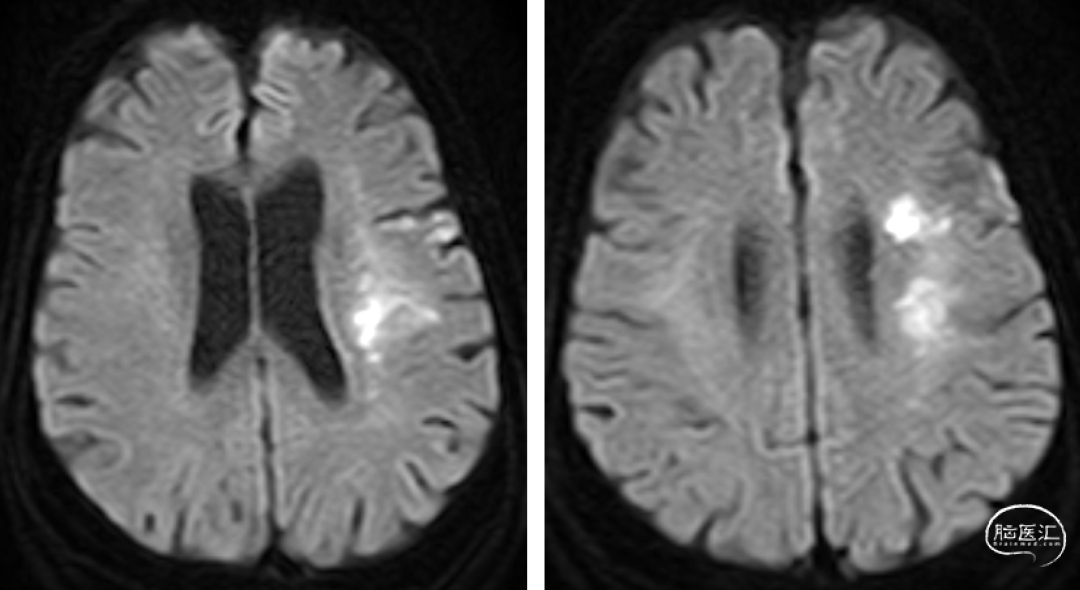

入院前头颅MR(2-22 8:30AM)。

患者急性起病,最初起病NIHSS评分3分,最初头颅MRA可见LM1大血管闭塞,但仍有血管残端,结合DWI图像,考虑血栓在分叉部未完全堵塞血管;但后来患者突然加重,考虑侧枝衰竭或血栓位移或二次心源性栓塞可能性大(有房颤病史),计划首先ADAPT抽吸,再Solumbra技术抽拉结合取栓治疗,视情况必要时补充技术。